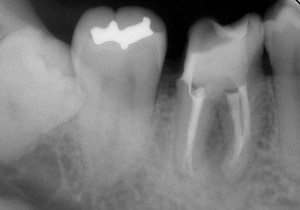

レントゲン写真で確認すると

根の先に病気がある。かぶせ物の適合も悪そう。

そして・・・

う~ん・・・(汗) どうも治療器具が折れて中に残っていそう(T_T) そのため、根の先まで治療が行えていない。